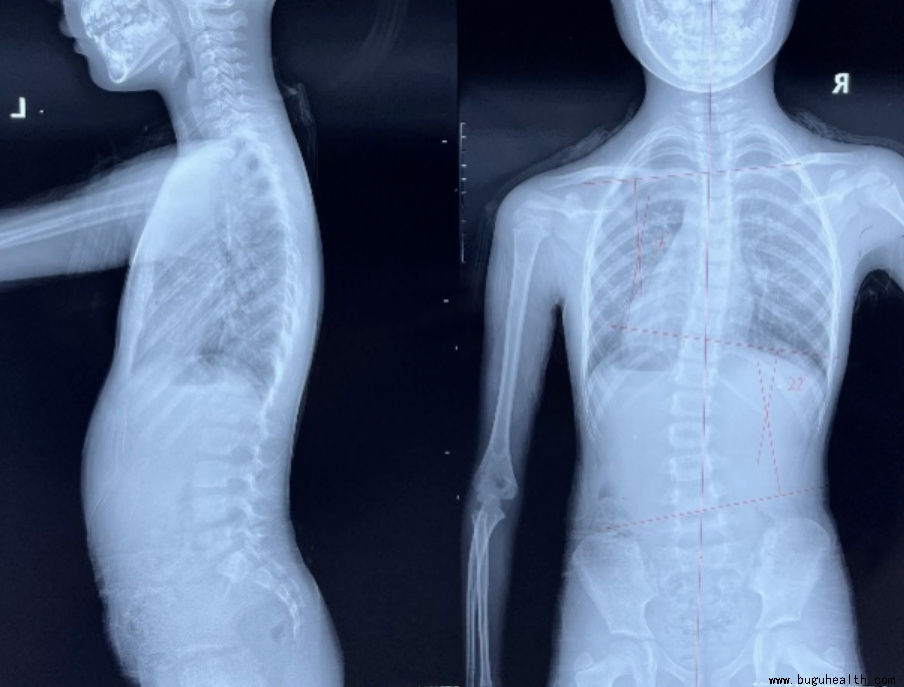

脊柱侧弯(又称脊柱侧凸),是以脊柱的某一段持久地偏离身体中线,使脊柱向侧方凸出弧形或“S”形为主要表现的疾病。

严重的畸形不仅影响孩子外观,例如高低肩、含胸驼背、剃刀背,这些都会导致自卑、抑郁、缺乏自信等心里情绪问题,还会给孩子造成心肺功能降低,例如出现呼吸困难或者呼吸急促等问题,也会出现神经压迫,当侧弯到达一定的程度时神经就会受到压迫,会出现麻木疼痛等相关神经症状,如果侧弯继续加大,在纵向力的冲击下可能会发生脊柱骨折,导致脊髓损伤可能瘫痪,甚至危及生命。

脊柱侧弯的诊断标准是cobb角大于10度,所以当家长自己在家用六部筛查法怀疑自己孩子有可能有脊柱侧弯的时候,你就应该带孩子到医院找专业的医生进行进一步确诊,当我们通过影像学确诊为脊柱侧弯的时候,我们会根据孩子的年龄、侧弯度数来建议目前孩子适合的矫正方法,目前对于脊柱侧弯的矫正大致分为三种:一是康复训练即矫形体操;二是体操加矫形支具;三是手术。